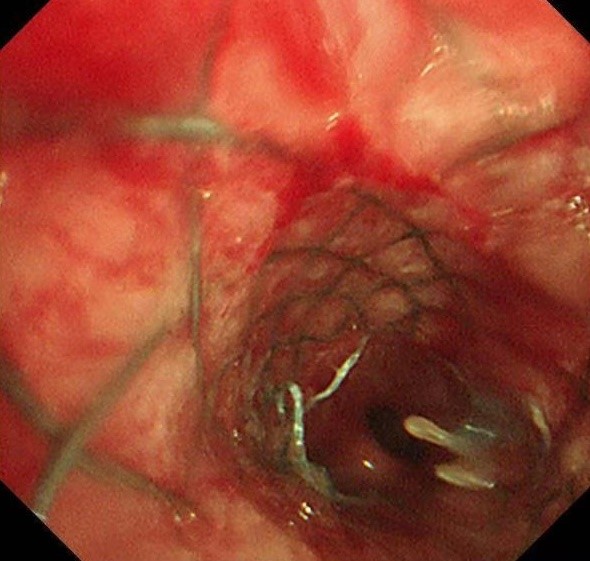

术中发现,右主支气管完全闭塞,肿瘤新生物广泛浸润;左主支气管混合性狭窄,狭窄率高达70%,并伴有黏膜浸润样改变。团队冷静而高效地操作,仅用不到1分钟便将支架精准置入目标位置。置入的可过活检孔道气管支架成功打开了左侧主支气管,同时确保上下叶开口通畅。患者呼吸困难立即减轻,胸闷气促的折磨被迅速解除。术后,丁女士激动地拉着蒋军红主任的手,激动着说:“已经三天三夜没能躺下睡觉了,谢谢你们让我又能喘口气!”

此次救治中,蒋军红主任团队采用了自主研发的TTS技术(Through-The-Scope)气道支架。这种技术与传统的导丝引导气道支架相比,具有以下显著优势:

·操作简便、高效安全:支架植入可以在软性支气管镜下快速完成;